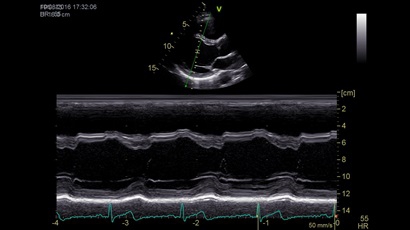

Анатомический М-режим:

Да

M-режим:

• Режимы: 4D, 2D (B-режим), цветной допплеровский режим, режим энергетического допплера, M-режим, цветной M-режим, спектральные режимы импульсно-волнового допплера (PW) и непрерывно-волнового допплера (CW), визуализация скорости движения тканей.

• Анатомический М-режим (АММ).

• Криволинейный анатомический М-режим (CAMM).